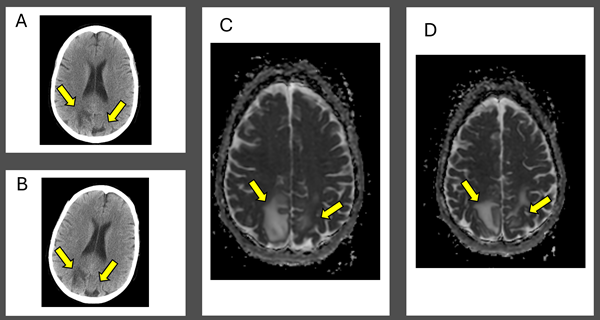

At this point, further workup was initiated: complete metabolic panel, magnesium, phosphorous, thyroid stimulating hormone (TSH) level, ethanol, urinalysis (UA), and urine drug screen (UDS) were obtained, which were notable for improved creatinine of 1.0, calcium of 7.8, mildly decreased TSH of 0.384, nitrite positive UA, and UDS positive for barbiturates, benzodiazepines, and opiates. Non-contrast head CT demonstrated bilateral vasogenic edema in the posterior parietal lobes read as concerning for posterior reversible encephalopathy syndrome (PRES; see Figure 1A). The patient was admitted after consultation with neurology for observation and an MRI.

A few hours after admission she ultimately eloped during shift change. She returned to the same ED the next day after being found unresponsive outside again, was given Narcan en route as well as in the ED for bradypnea, and ultimately started on a naloxone drip, though she remained saturating well on room air. The initial temperature was 97.8°F and the initial BP was 121/83. Repeat head CT demonstrated the same vasogenic edema as seen previously (see Figure 1B). The patient was admitted again and remained normotensive. MRI with and without contrast demonstrated expansile T2/FLAIR hyperintense signal in the posterior frontal and parietal lobes, favored to be PRES (see Figure 1C and D).

Figure 1: Computed Tomography and Magnetic Resonance Imaging Demonstrating Posterior Reversible Encephalopathy Syndrome (PRES) Figure Caption: Initial (A) and next-day (B) CT imaging of concerning for PRES, with bilateral parietal vasogenic edema noted. MRI demonstrated expansile T2/FLAIR hyperintense signal in the posterior frontal and parietal lobes, favored to be PRES (C and D). Arrows correspond to areas of interest.

Initial (A) and next-day (B) CT imaging of concerning for PRES, with bilateral parietal vasogenic edema noted. MRI demonstrated expansile T2/FLAIR hyperintense signal in the posterior frontal and parietal lobes, favored to be PRES (C and D). Arrows correspond to areas of interest.